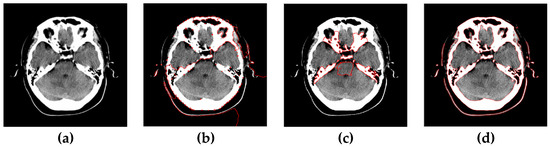

4.5. Segmentation of Medical Images